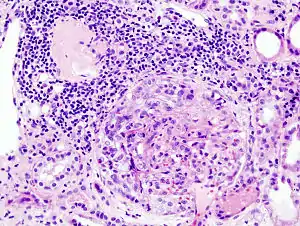

RPGN can be classified into three types, based upon the immunofluorescence patterns:[3]

Type I

Accounting for approximately 3[11]% of RPGN, type I RPGN, also called anti-GBM glomerulonephritis, is characterized by the presence of autoantibodies directed against type IV collagen (specifically, the noncollagenous region of its α3 chain)[2] in the glomerular basement membrane (GBM). Some cases are associated with antibodies directed against the basement membrane of lung alveoli, producing Goodpasture syndrome. The majority of type I disease, however, features anti-GBM antibodies alone; these cases are considered idiopathic.[2]

Type II

Characterized by deposition of immune complexes in glomerular tissues, type II RPGN accounts for 40[12]% of cases. Any immune complex disease—including systemic lupus erythematosus, acute proliferative glomerulonephritis, Henoch–Schönlein purpura, and IgA nephropathy—that involves the glomerulus may progress to RPGN if severe enough.[2]

Type III

Also known as pauci-immune RPGN, type III RPGN accounts for 55% of RPGN and features neither immune complex deposition nor anti-GBM antibodies. Instead, the glomeruli are damaged in an undefined manner, perhaps through the activation of neutrophils in response to ANCA. Type III RPGN may be isolated to the glomerulus (primary, or idiopathic) or associated with a systemic disease (secondary). In most cases of the latter, the systemic disease is an ANCA-associated vasculitis such as granulomatosis with polyangiitis, microscopic polyangiitis or eosinophilic granulomatosis with polyangiitis.[2]